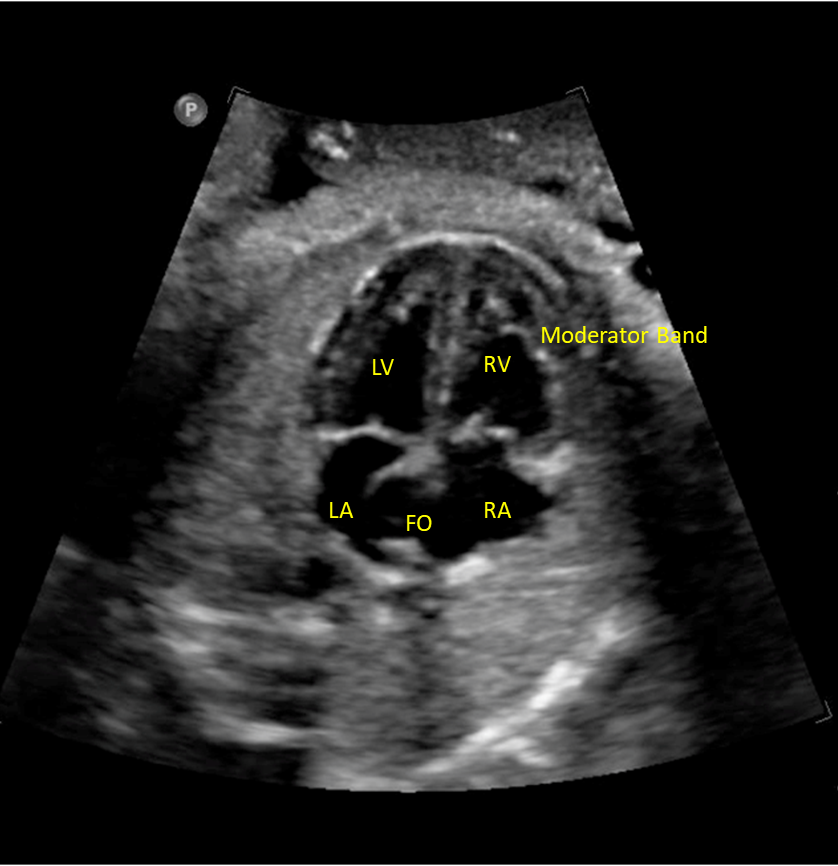

normally what is closest to anterior abdominal wall

right ventricle

what is closest to spine

left atrium

blood flow through foramen ovale

right to left

where is moderator band located

tricuspid valve on ____ side

right

mitral valve on ____ side

left

4 chamber heart should sit at a ___ degree angle and take up about ____ of the chest

45 degree

1/3

___ of the herat located in left chest with apex pointing ____

2/3